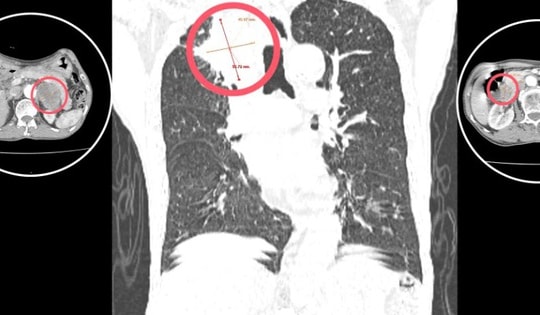

Tức ngực khi vận động, một thanh niên đi khám và phát hiện có khối u khổng lồ

Thấy tức ngực khi vận động và đi khám, một thanh niên Quảng Ninh được phát hiện có khối u trung thất cấu trúc hỗn hợp, kích thước khổng lồ ở lồng ngực.

Người đàn ông 42 tuổi mang khối u nặng 3,6kg trong lồng ngực mà không biết

Khối u trung thất khổng lồ, có kích thước lên tới 30x20 cm, nặng 3,6 kg. Đây là một trong những khối u lớn hiếm gặp trong y văn, đe dọa nghiêm trọng đến chức năng hô hấp của người bệnh.